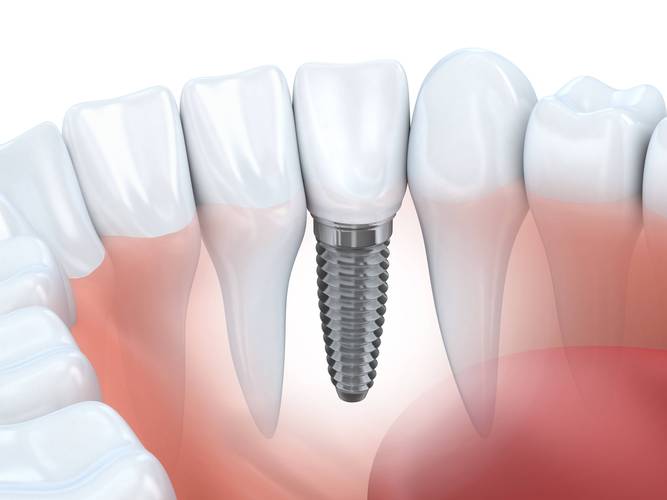

📐 三、 种植体结构示意图(理解关键部件)

虽然你问的是“种植体图片”,但理解其结构对认识图片很重要,搜索“dental implant anatomy diagram”可以找到很多清晰的示意图,通常包括:

- 种植体: 植入牙槽骨的部分(Fixture/Implant Body)。

- 基台: 连接种植体和牙冠的中间部件(Abutment)。

- 愈合帽/封闭螺丝: 手术初期覆盖在种植体顶部的螺丝(Healing Cap/Cover Screw)。

- 牙冠: 最终恢复牙齿形态和功能的修复体(Crown)。

- 牙龈成形器: 引导牙龈长成理想形态(Gingival Former)。